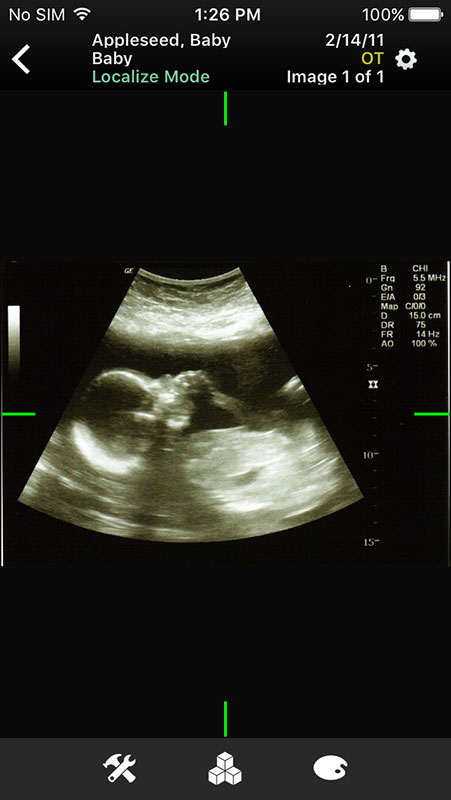

These sample images feature same imaginary patients and cases from the Mobile MIM app and contain X-ray, PETCT, MR, and ultrasound scans, alongside the name of the procedure.

Just like in Mobile MIM app, images open in multi-planar view allowing users to choose series depending on the type of imaging technique, add annotation, or measure the image.